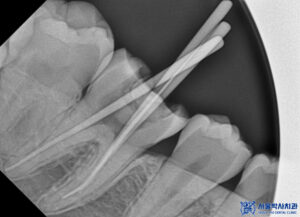

이렇게 신경치료를 진행하며

먼저 충치 제거 후,

감염된 치아 내부를

철저히 청소하고 소독하였습니다.

이후, 치아의 신경을 제거하고

깨끗하게 정리한 뒤,

빈 공간을 충전재로 채워

치아를 밀봉했습니다.

또한 오른쪽 아래 큰 어금니도

내부로 충치가 심한 상태로

신경치료를 함께 진행하기로 하였습니다.

똑같이 충치를 제거하고

감염된 내부를 깨끗하게 세척한 후

치아 내부의 빈 공간을 특수한 충전재로 채워

밀봉하여 치아가 더 이상

감염되지 않도록 했습니다.